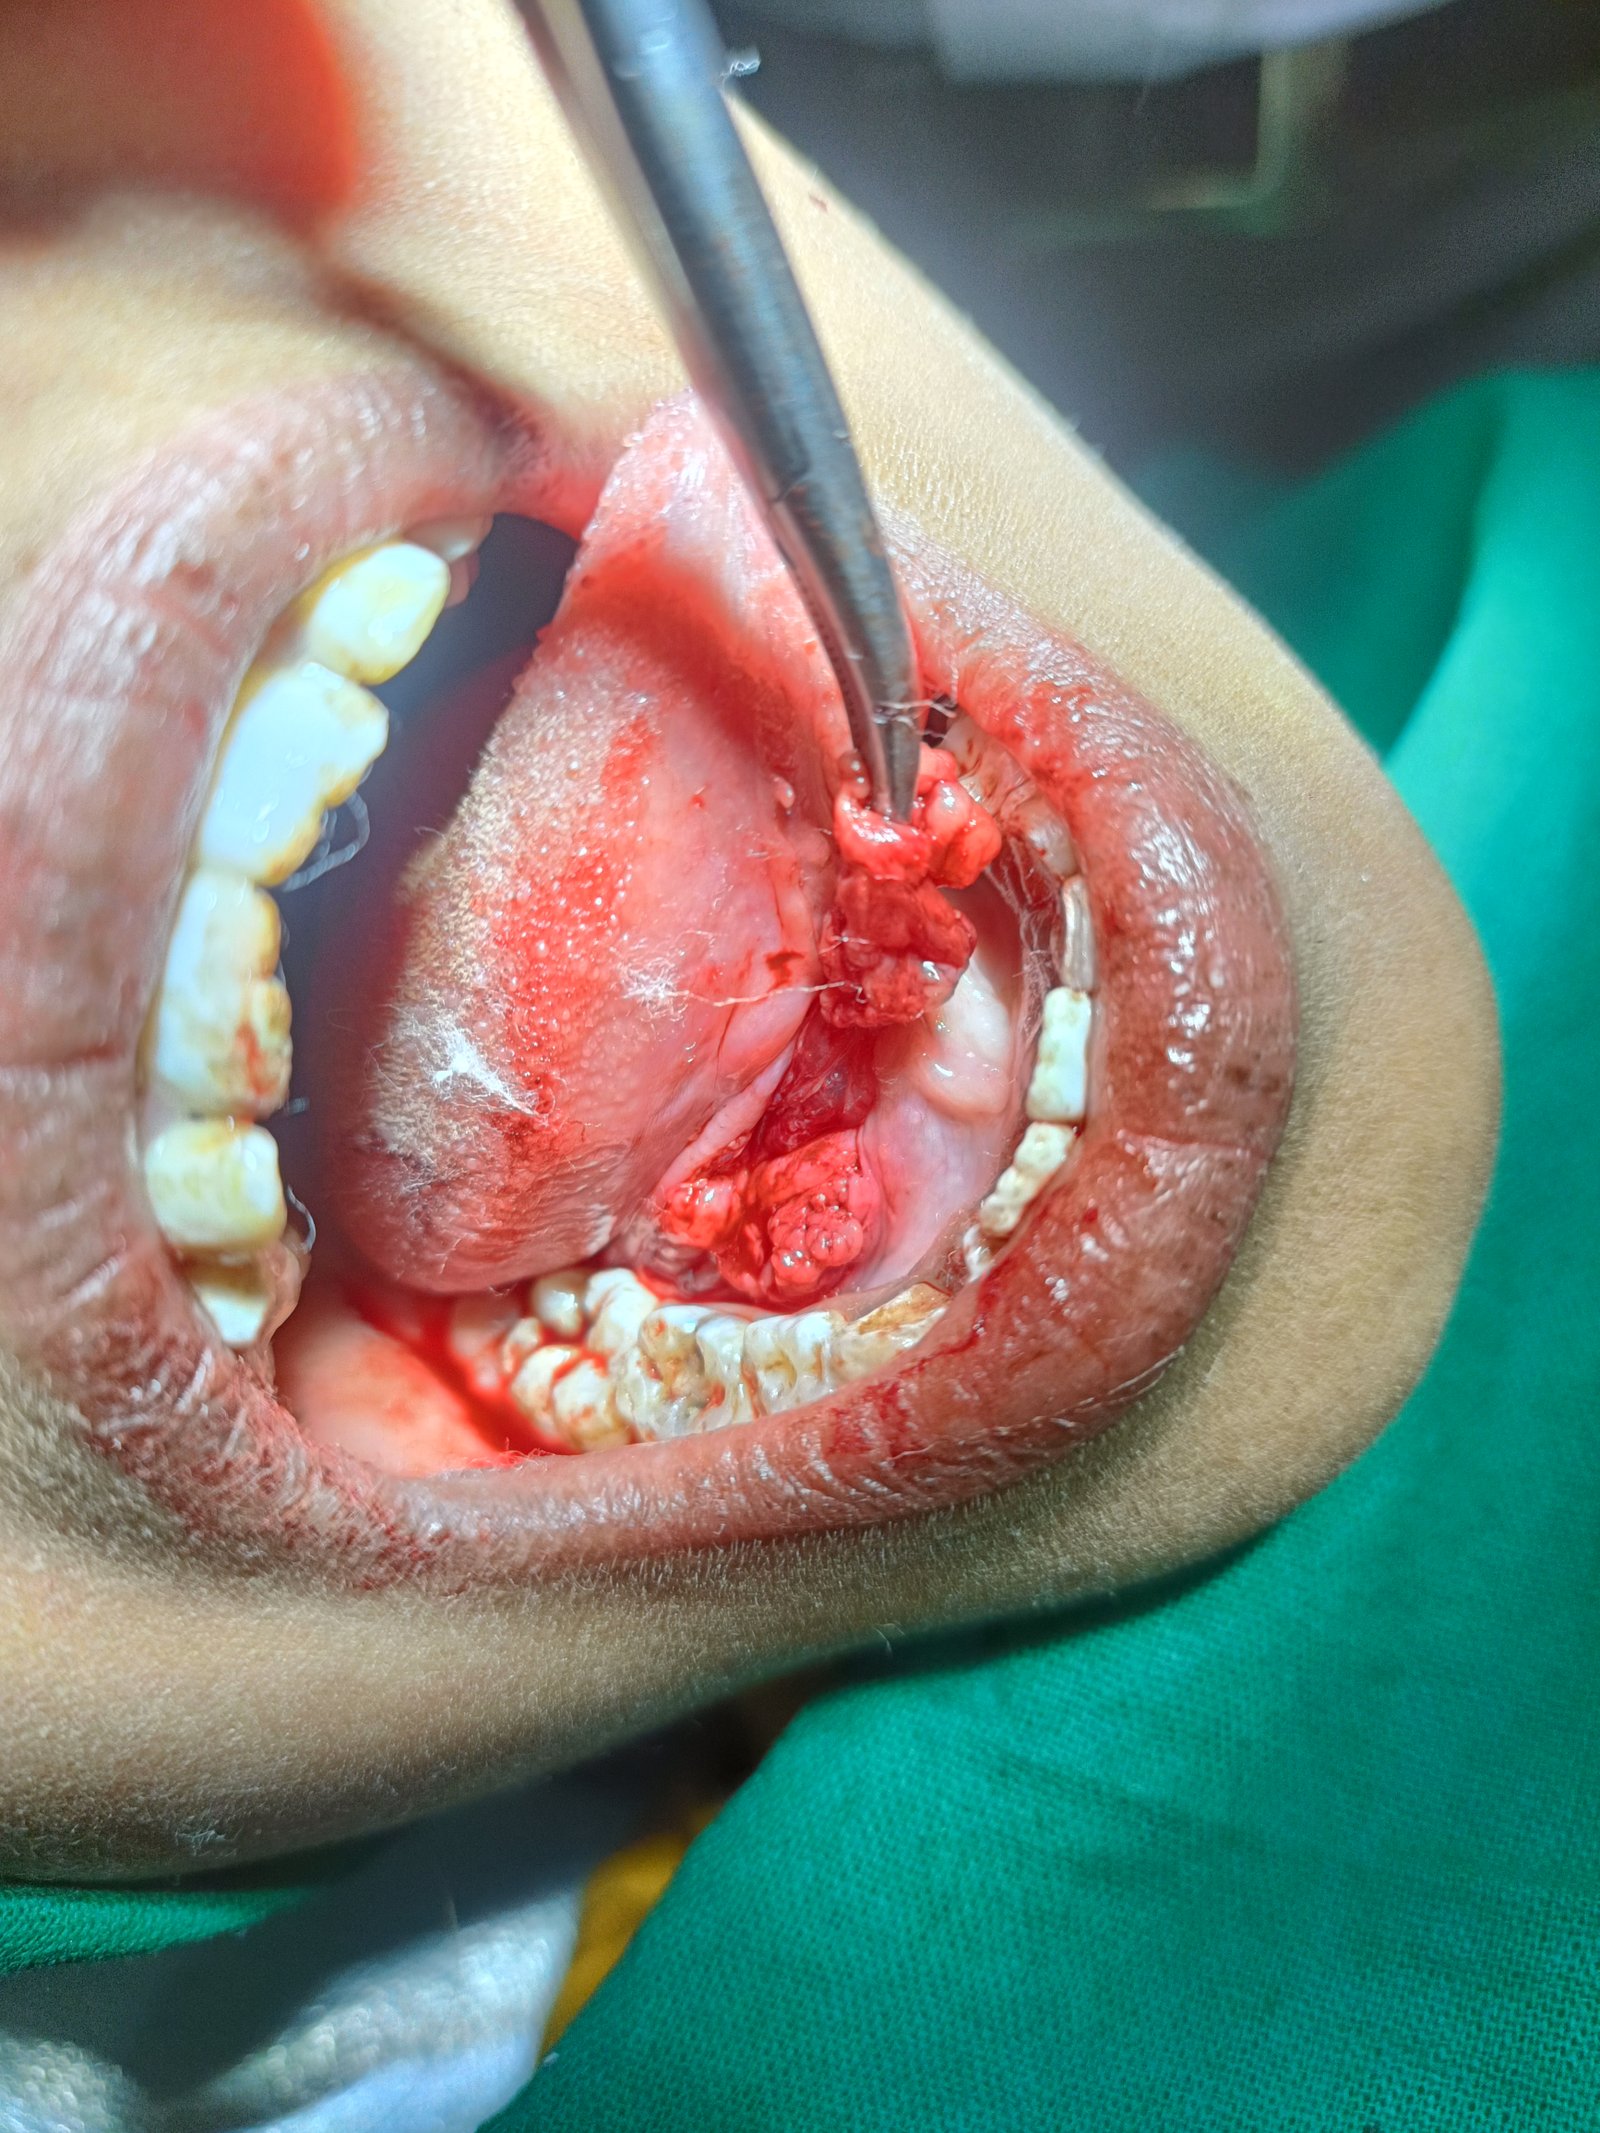

ЁЯПе рдзрд╛рд░рд╛рд╢рд┐рд╡ рдЬрд┐рд▓реНрд╣реНрдпрд╛рддреАрд▓ рдкреНрд░рд╕рд┐рджреНрдз рдбреЗрдВрдЯрд▓ рд╣реЙрд╕реНрдкрд┐рдЯрд▓ & рдлреЗрд╢рд┐рдпрд▓ рдЯреНрд░реЙрдорд╛ рдХреЗрдЕрд░ рд╡ рдЗрдореНрдкреНрд▓рд╛рдВрдЯ рд╕реЗрдВрдЯрд░ ЁЯПе ЁЯПердЕрддреНрдпрд╛рдзреБрдирд┐рдХ рдбрд┐рдЬрд┐рдЯрд▓ рдПрдХреНрд╕-рд░реЗ ЁЯПердЗрдВрдЯреНрд░рд╛ рдУрд░рд▓ рдХреЕрдореЗрд░рд╛ рджреНрд╡рд╛рд░реЗ рддрдкрд╛рд╕рдгреА ЁЯж╖рдЕрд▓реНрдЯреНрд░рд╛рд╕реЛрдирд┐рдХ рдорд╢реАрдирджреНрд╡рд╛рд░реЗ рджрд╛рдд рд╕рд╛рдл рдХрд░рдгреЗ ЁЯж╖рдХреГрддреНрд░рд┐рдо рджрдВрддрд░реЛрдкрдг ЁЯж╖рдЕрдХреНрдХрд▓рджрд╛рдбреЗ рд╡рд░реАрд▓ рд╢рд╕реНрддреНрд░рдХреНрд░рд┐рдпрд╛ ЁЯж╖рдЬрдмрдбреНрдпрд╛рдВрдЪреЗ рдлреНрд░реЕрдХреНрдЪрд░ рд╡рд░реАрд▓ рд╢рд╕реНрддреНрд░рдХреНрд░рд┐рдпрд╛ ЁЯзмрдЕрддреНрдпрд╛рдзреБрдирд┐рдХ рдкрджреНрдзрддреАрдиреЗ рджрд╛рддрд╛рдВрдЪреНрдпрд╛ рдирд╕рд╛ рд╡рд░реАрд▓ рдЙрдкрдЪрд╛рд░ ЁЯзмрддреЛрдВрдбрд╛рддреАрд▓ рдореМрдЦрд┐рдХ рд╢рд╕реНрддреНрд░рдХреНрд░рд┐рдпрд╛ ЁЯзмрд╕рдВрдкреВрд░реНрдг рдХрд┐рдВрд╡рд╛ рдЕрдВрд╢рддрдГ рдХрд╡рд│реА рдмрд╕рд╡рдгреЗ ЁЯзмрд╡реЗрдбреЗрд╡рд╛рдХрдбреЗ рджрд╛рдд рд╕рд░рд│ рдХрд░рдгреЗ

ЁЯПе рдлреЗрд╢рд┐рдпрд▓ рдЯреНрд░реЙрдорд╛ рдХреЗрдЕрд░ рд╡ рдЗрдореНрдкреНрд▓реЗрдВрдЯ рд╕реЗрдВрдЯрд░

ЁЯПе рддреЛрдВрдбрд╛рддреАрд▓ рдореМрдЦрд┐рдХ рд╢рд╕реНрддреНрд░рдХреНрд░рд┐рдпрд╛ рд╕реНрдкреЗрд╢рд╛рд▓рд┐рд╕реНрдЯ